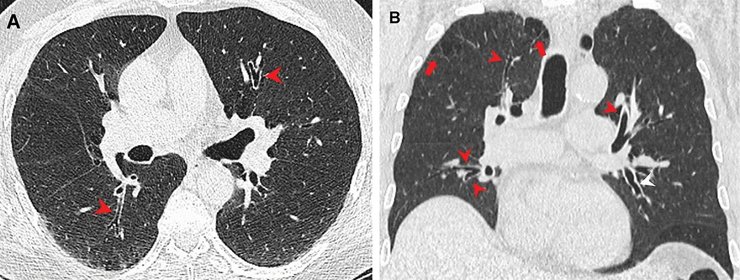

Исследование в журнале Radiology утверждает, что у курильщиков марихуаны чаще встречается эмфизема. Во время этого в легких увеличивается объем альвеол из-за разрушения перепонок между ними. При этом заболевании тяжело делать выдох. Кроме того, легкие становятся безжизненными. Ученые предполагают, что результаты исследования могли быть обусловлены тем, что дым марихуаны попадает в легкие нефильтрованным.

Ученые уже многое знают о влиянии сигарет на легкие, в отличие от марихуаны. Автор исследования Жизель Рева предположила, что курение "травки" накапливает в разы больше частиц в легких, чем обычная табачная сигарета. Чтобы проверить это утверждение, она и ее коллеги сравнили КТ 56 курильщиков марихуаны с результатами 57 некурящих, а также группой из 33 курильщиков табака.

Обнаружили, что три четверти или 75% курильщиков марихуаны получили эмфизему. Зато ценители табака получили более низкий результат – 67%.

Также ученые отмечают, что воспаление дыхательных путей было более распространенным именно у курильщиков марихуаны. Похожая ситуация была с гинекомастией – увеличение грудной железы у мужчин. Соотношение в процентах курильщиков табака и марихуаны было 11 к 38. Похожие результаты получили во время соответствующих по возрасту подгрупп тоже.